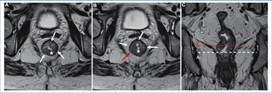

En sentido caudal, debemos identificar la unión ano-rectal y el margen anal, para de esa forma identificar el canal anal. Esta unión ano-rectal se encuentra en íntima relación con el anillo puborrectal y la porción proximal del esfínter anal externo, para identificar esta se toma como punto de referencia una línea imaginaria que une la cara inferior del pubis y el sacro3 (Fig. 5).

Otra estructura que el radiólogo debe reconocer es el esfínter anal. Este está compuesto por una capa interna, el esfínter anal interno, que es continuación de la capa muscular interna del recto; rodeado por una capa externa de músculo estriado, el esfínter anal externo, el cual se encuentra en relación con los músculos elevadores del ano y del anillo puborrectal. Ambas capas se encuentran separadas por un espacio de tejido adiposo de grosor variable: el espacio interesfin teriano7 (Fig. 6).